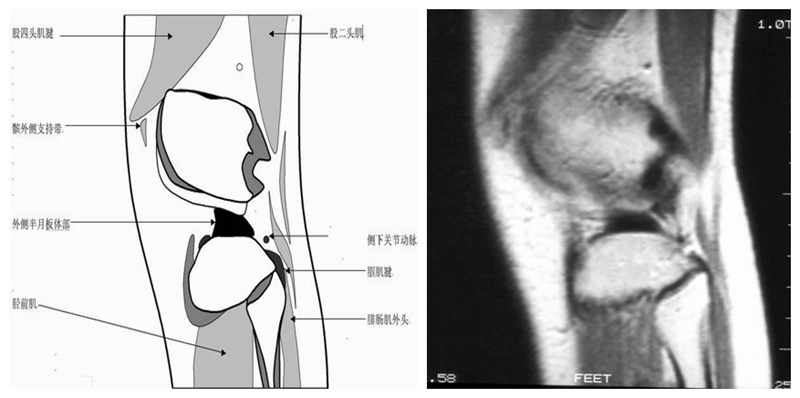

矢状位解剖第五层

矢状位解剖第六层